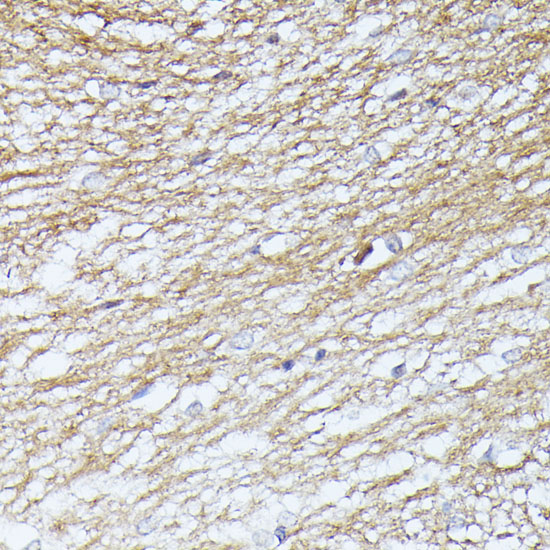

Immunohistochemistry of paraffin-embedded rat brain using SEPT5 at dilution of 1:100 (40x lens).

Immunohistochemistry of paraffin-embedded mouse brain using SEPT5 at dilution of 1:100 (40x lens).